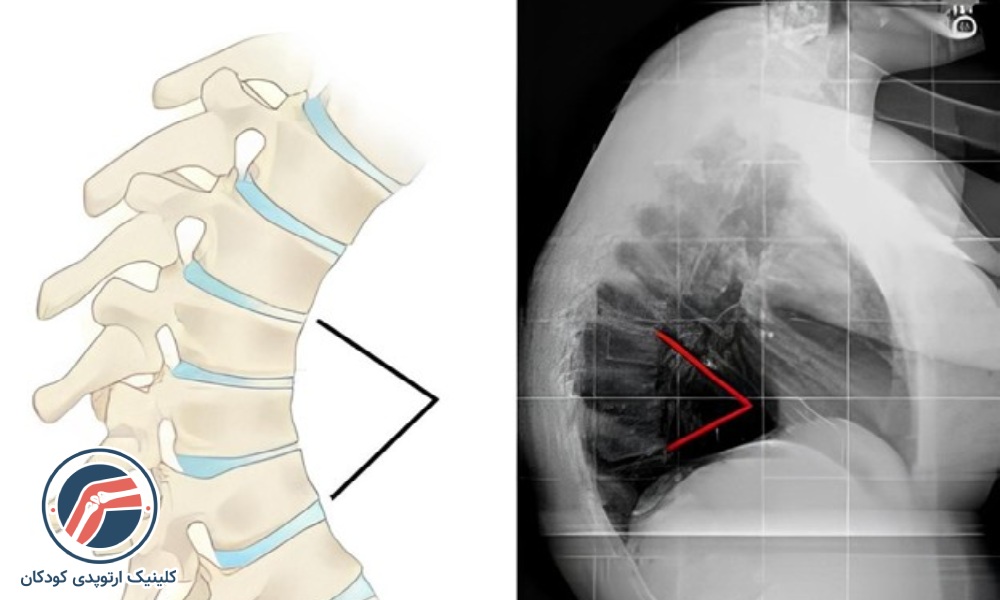

- کیفوز شوئرمن: عارضه کیفوز شوئرمن یک نوع ناهنجاری ستون فقرات است که در آن مهرهها بهجای اینکه مستطیلی باشند، شکل ذوزنقهای و غیرعادی پیدا میکنند. به همین دلیل، دیسکها در قرارگیری بین مهرهها دچار مشکل شده و باعث خمیدگی ستون فقرات میشوند. منحنی ایجاد شده در اثر کیفوز شوئرمن معمولاً تیز و زاویهدار است. این عارضه روی ساختار قفسه سینه هم تأثیر میگذارد و میتواند باعث بروز مشکلات تنفسی شود. این مهرههای بدشکل اغلب باعث ایجاد فرورفتگیهایی در استخوانهای مهره ميشوند و ممکن است باعث بروز عارضههای دیگر شوند. کیفوز شوئرمن اغلب در طول سالهای نوجوانی مشاهده میشود.

- تصویربرداری: تصویربرداری به مشخصشدن دقیقتر انحنا و میزان قوس کمر کمک میکند. معمولاً پزشکان کودکانی که دارای کیفوز خفیف هستند را بهدقت تحتنظر میگیرند و در دورههای ۶ ماهه از ستون فقرات آنها بهوسیله اشعهایکس یا MRI تصویربرداری میکنند. در بزرگسالان علاوه بر تصویربرداری ممکن است که به آزمایش خون و آزمایش تراکم استخوان نیز برای تشخیص دقیقتر نیاز باشد.